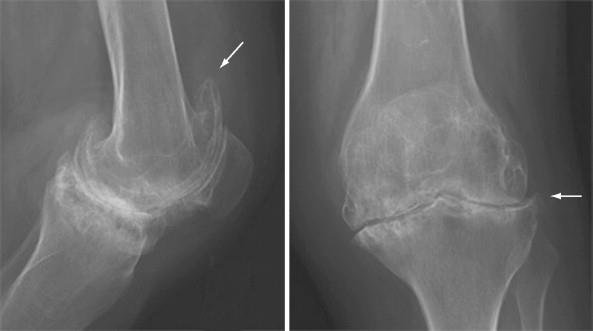

Rheumatoid Arthritis

RA with secondary OA and severe cartilage loss. Radiographs of the knee show severe uniform loss of the cartilage space. The symmetry of medical and lateral compartment narrowing suggests an underlying inflammatory condition. The changes of OA with osteophytes (arrows) and subchondral sclerosis are noted. Soft tissue swelling and a suprapatellar knee effusion are also present.

Rheumatoid arthritis (RA) is a systemic autoimmune disease that can affect various joints in the body, including the knee. In the knee, RA can lead to outer knee pain due to inflammation and damage to the joint.